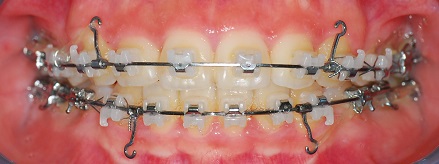

치아 사진 먼저 보여드릴게요

정면 사진

여기도 아주 조금 남은 공간이 보이시나요?

찾기 힘들정도로 조금 남앗어요ㅎㅎㅎ

뻐드러 졋던 이가 많이 들어갔어요